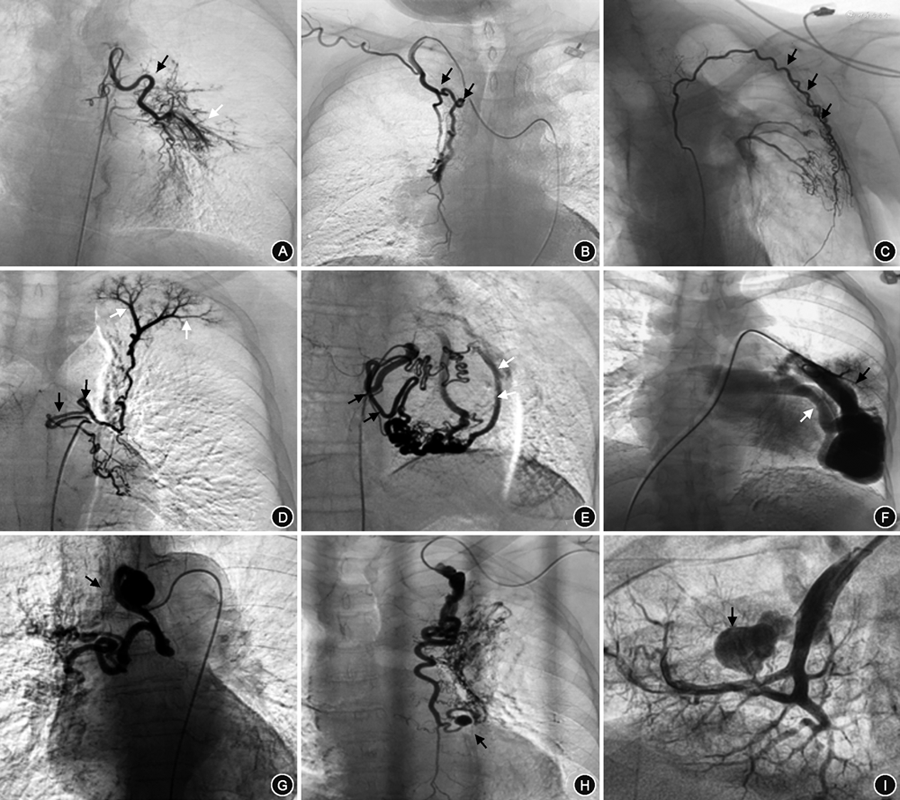

所有患者术中DSA均发现支气管动脉(bronchial artery,BA)血管增粗、迂曲,末梢分支增多紊乱,病灶区域血管呈网状或丛状分布(图2A),其中,29.6%为异位起源BA(图2B)。774例(63.9%)患者存在非支气管性体动脉(non-bronchial systemic artery,NBSA)异常并参与病灶部位供血(图2C)。1 092例(90.2%)患者存在体动脉-肺循环异常交通。包括肋间动脉-肺动脉瘘(图2C),食管固有动脉-肺动脉瘘(图2D);BA-肺静脉瘘(图2E);肺动-静脉瘘(图2F);143例(11.8%)有动脉瘤或瘤样扩张。包括支气管动脉瘤(图2G);非支气管性胸廓内动脉瘤(图2H);肺动脉假性动脉瘤(图2I)。单纯肺动脉高压引起的咯血,以第一大类先天性心脏病引起的肺动脉高压为常见,责任血管可涉及锁骨下动脉分支、胸、腹主动脉分支(支气管动脉、肋间后动脉、膈下动脉、食管固有动脉),主干迂曲增粗、末梢紊乱,责任血管床大多沿肺门周围分布(图3)。白塞病的靶血管分布在以肺动脉灌注较差位置的周围体动脉的迂曲、扩张及末梢紊乱,多发的体-肺动脉瘘形成,责任血管末梢网血管丰富(图4)。

纳入的1 211例咯血患者,术中探及的责任血管大部分完成栓塞,5例11支血管因栓塞禁忌未予以栓塞。单用PVA颗粒栓塞59例,PVA和GS颗粒联合栓塞1 009例(83.3%)。143例(11.8%)动脉瘤或瘤样扩张均使用弹簧圈进行栓塞。共栓塞引起咯血责任血管6 540支;其中最少者栓塞1支血管,最多者栓塞31支血管。例均栓塞的血管支数为(5.4±3.7)支。所有患者均有来自BA的咯血,共栓塞BA 3 027支,栓塞BA(2.5±1.0)支,其中29.6%为异位起源BA,以主动脉弓(35.8%)、锁骨下动脉(30%)和胸廓内动脉(27.9%)起源多见。正常起源BA中,栓塞左侧BA、右侧BA、左右共干BA和支肋共干BA分别为30.6%、10.4%、25.9%、33.1%。774例(63.9%)患者存在来自NBSA的咯血,栓塞NBSA(3.5±2.0)支,其中以胸廓内动脉(24.5%)、膈下动脉(24.4%)多见(图5)。其中,4例肺动脉高压患者共栓塞责任血管24支,正常起源BA 10支,异位起源BA 8支,NBSA 6支(包括胸廓内动脉、肋间后动脉)。2例白塞病患者共栓塞责任血管 21支,正常起源BA 6支,异位起源BA 2支,NBSA 13支(包括胸廓内动脉、甲状颈干、肋间后动脉、胸上动脉、膈下动脉、食管固有动脉)。